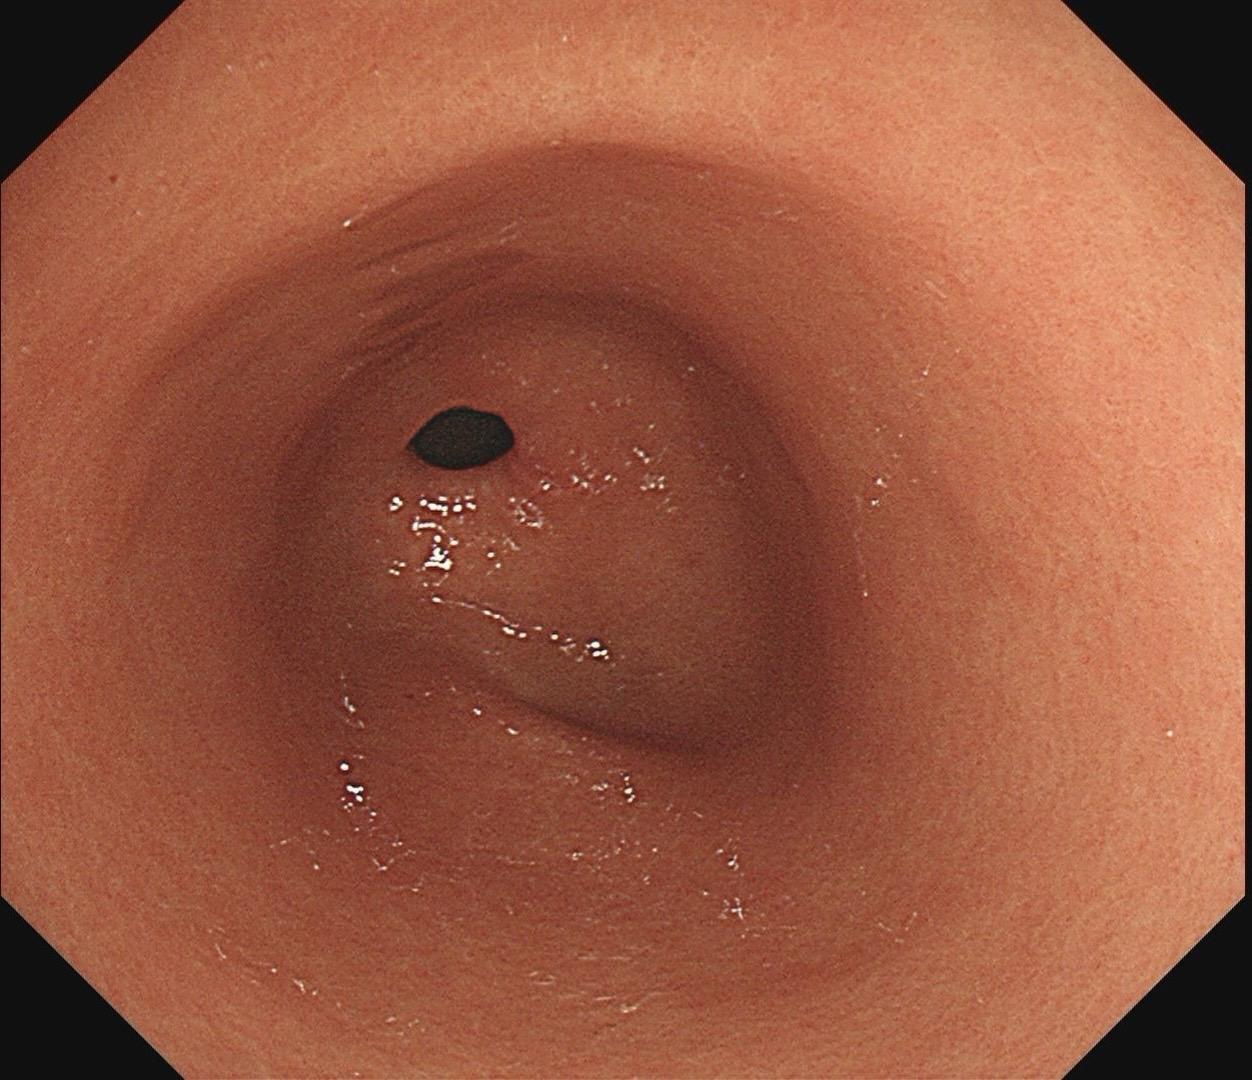

低位早期直肠Ca.男,37岁,大便带血1月,距齿状线2cm,ESD切除...